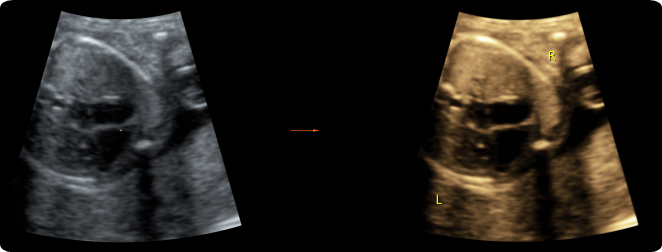

What is the best way to view Transposition of Great Vessels?

Parasternal short-axis

4 chamber view

With Transposition of Great Vessels, the ____ ____ ____ may appear normal.

4-chamber view

Will see the vessels run parallel when we are attempting to obtain our 3-vessel view